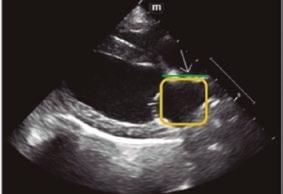

Utilidad clínica de la ecografía pulmonar y cardiaca en urgencias